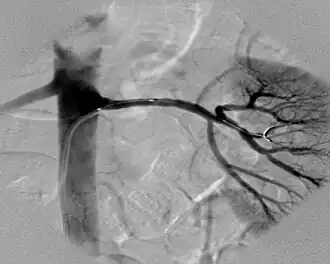

Angiografia ou angiograma é o método de realização de um exame radiográfico dos vasos sanguíneos, por meio da injeção de contraste radiopaco no ambiente intravascular.

O nome vem do grego agghéion (vaso) e grafo (escrever).[1] Tem o objetivo de fornecer um "mapa" vascular, que facilitará a localização de anormalidades dos vasos e com isso o diagnóstico de determinadas patologias.

O procedimento é utilizado para ajudar a diagnosticar doenças como o infarto do miocárdio, placas ateroscleróticas calcificadas, acidente vascular cerebral (AVC), estenose da artéria renal, algum fator causativo da hipertensão, embolia pulmonar, doenças congênitas e adquiridas dos vasos sanguíneos chamada de contraste, pode ser injetada numa artéria ou veia introduzida num cateter inserido em uma artéria periférica e empurrada através do vaso até ser colocada no coração ou na origem das artérias do coração. Se tiverem provas de hipersensibilidade ao contraste, o procedimento é suspenso, pois pode haver reações alérgicas. Depois do procedimento, o paciente é monitorado para detectar hemorragias e lhe é recomendado que fique deitado por algumas horas. A angiografia das carótidas, às vezes, é levada a cabo quando o paciente sofre de ataques de isquemia passageiros (os sintomas de apoplexia com duração de menos de 24 horas) para ver se há uma obstrução ou estreitamento substancial em uma das artérias carótidas, que proporcionam o sangue ao cérebro. A angiografia cerebral é usada para verificar a presença de um aneurisma no cérebro ou ajudar a visualizar um tumor cerebral antes da cirurgia. Uma angiografia das artérias coronárias, combinada frequentemente com a cateterização cardíaca, é usada para identificar os lugares estreitos ou obstruções na artéria.

O contraste é geralmente injetado no vaso que vai ser examinado por um cateter fino na artéria femoral, braquial ou carótidas. O local é anestesiado e inserida uma agulha. Um cabo longo e fino é posto através da agulha. A agulha é retirada e o catéter é colocado, então, sobre o cabo no vaso sanguíneo. A ponta do cateter é guiada até o vaso a ser examinado e o contraste é injetada.